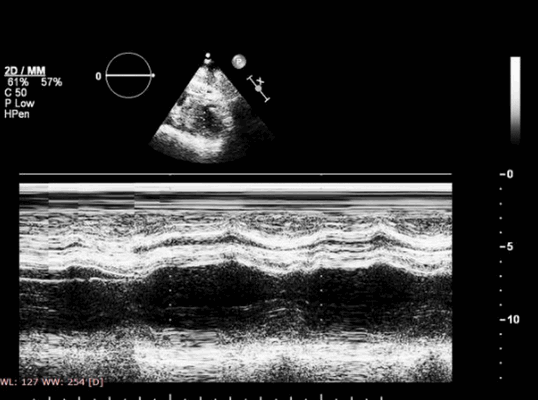

Оценка ишемии при эхокардиографии

Указанные изменения можно обнаружить с помощью двумерной эхокардиографии, но M-режим также чрезвычайно хорош, поскольку его высокая частота дискретизации делает его очень чувствительным к движению стенок и аномалиям утолщения. Важно, чтобы курсор располагался под углом 90° к стенке. Есть ограниченные области миокарда ЛЖ, которые можно исследовать в М-режиме - наиболее полезно задняя стенка и МЖП. Изменения обратимы, если ишемия кратковременная, например в покое, прием антиангинальных препаратов, проведенная вовремя чрескожная транслюминальная коронарная ангиопластика, тромболизис или аортокоронарное шунтирование (АКШ). Если кровоснабжение миокарда прервано более чем на 1 час, происходят необратимые изменения, включающие инфаркт миокарда и рубцевание.

Рис. 1. М-режим ТДИ восходящего отдела аорты. Левая парастернальная позиция по длинной оси на уровне 3 см выше аортального клапана. Метки движения стенок устанавливаются в пограничных точках окрашивания движения стенок к датчику (1) в фазу изометрического расслабления ЛЖ, и от датчика (2) в фазу изометрического сокращения ЛЖ. Диаметр аорты измеряется по внутренним краям стенки